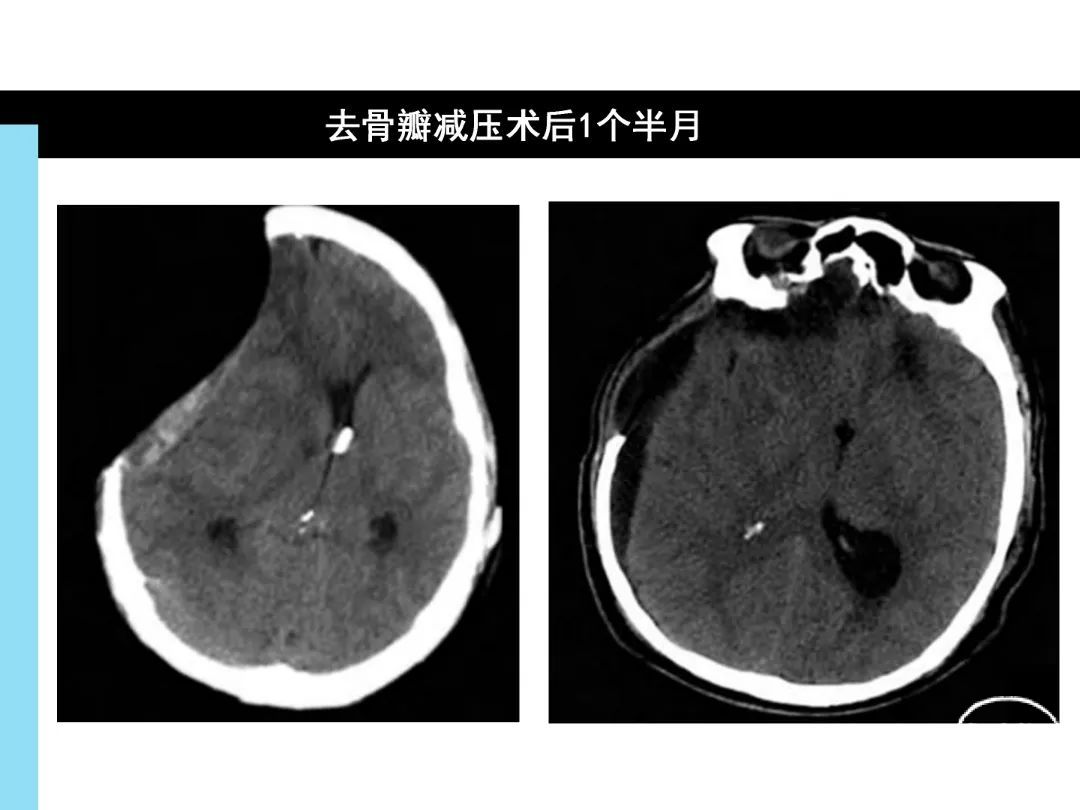

去骨瓣减压术后反常性脑疝